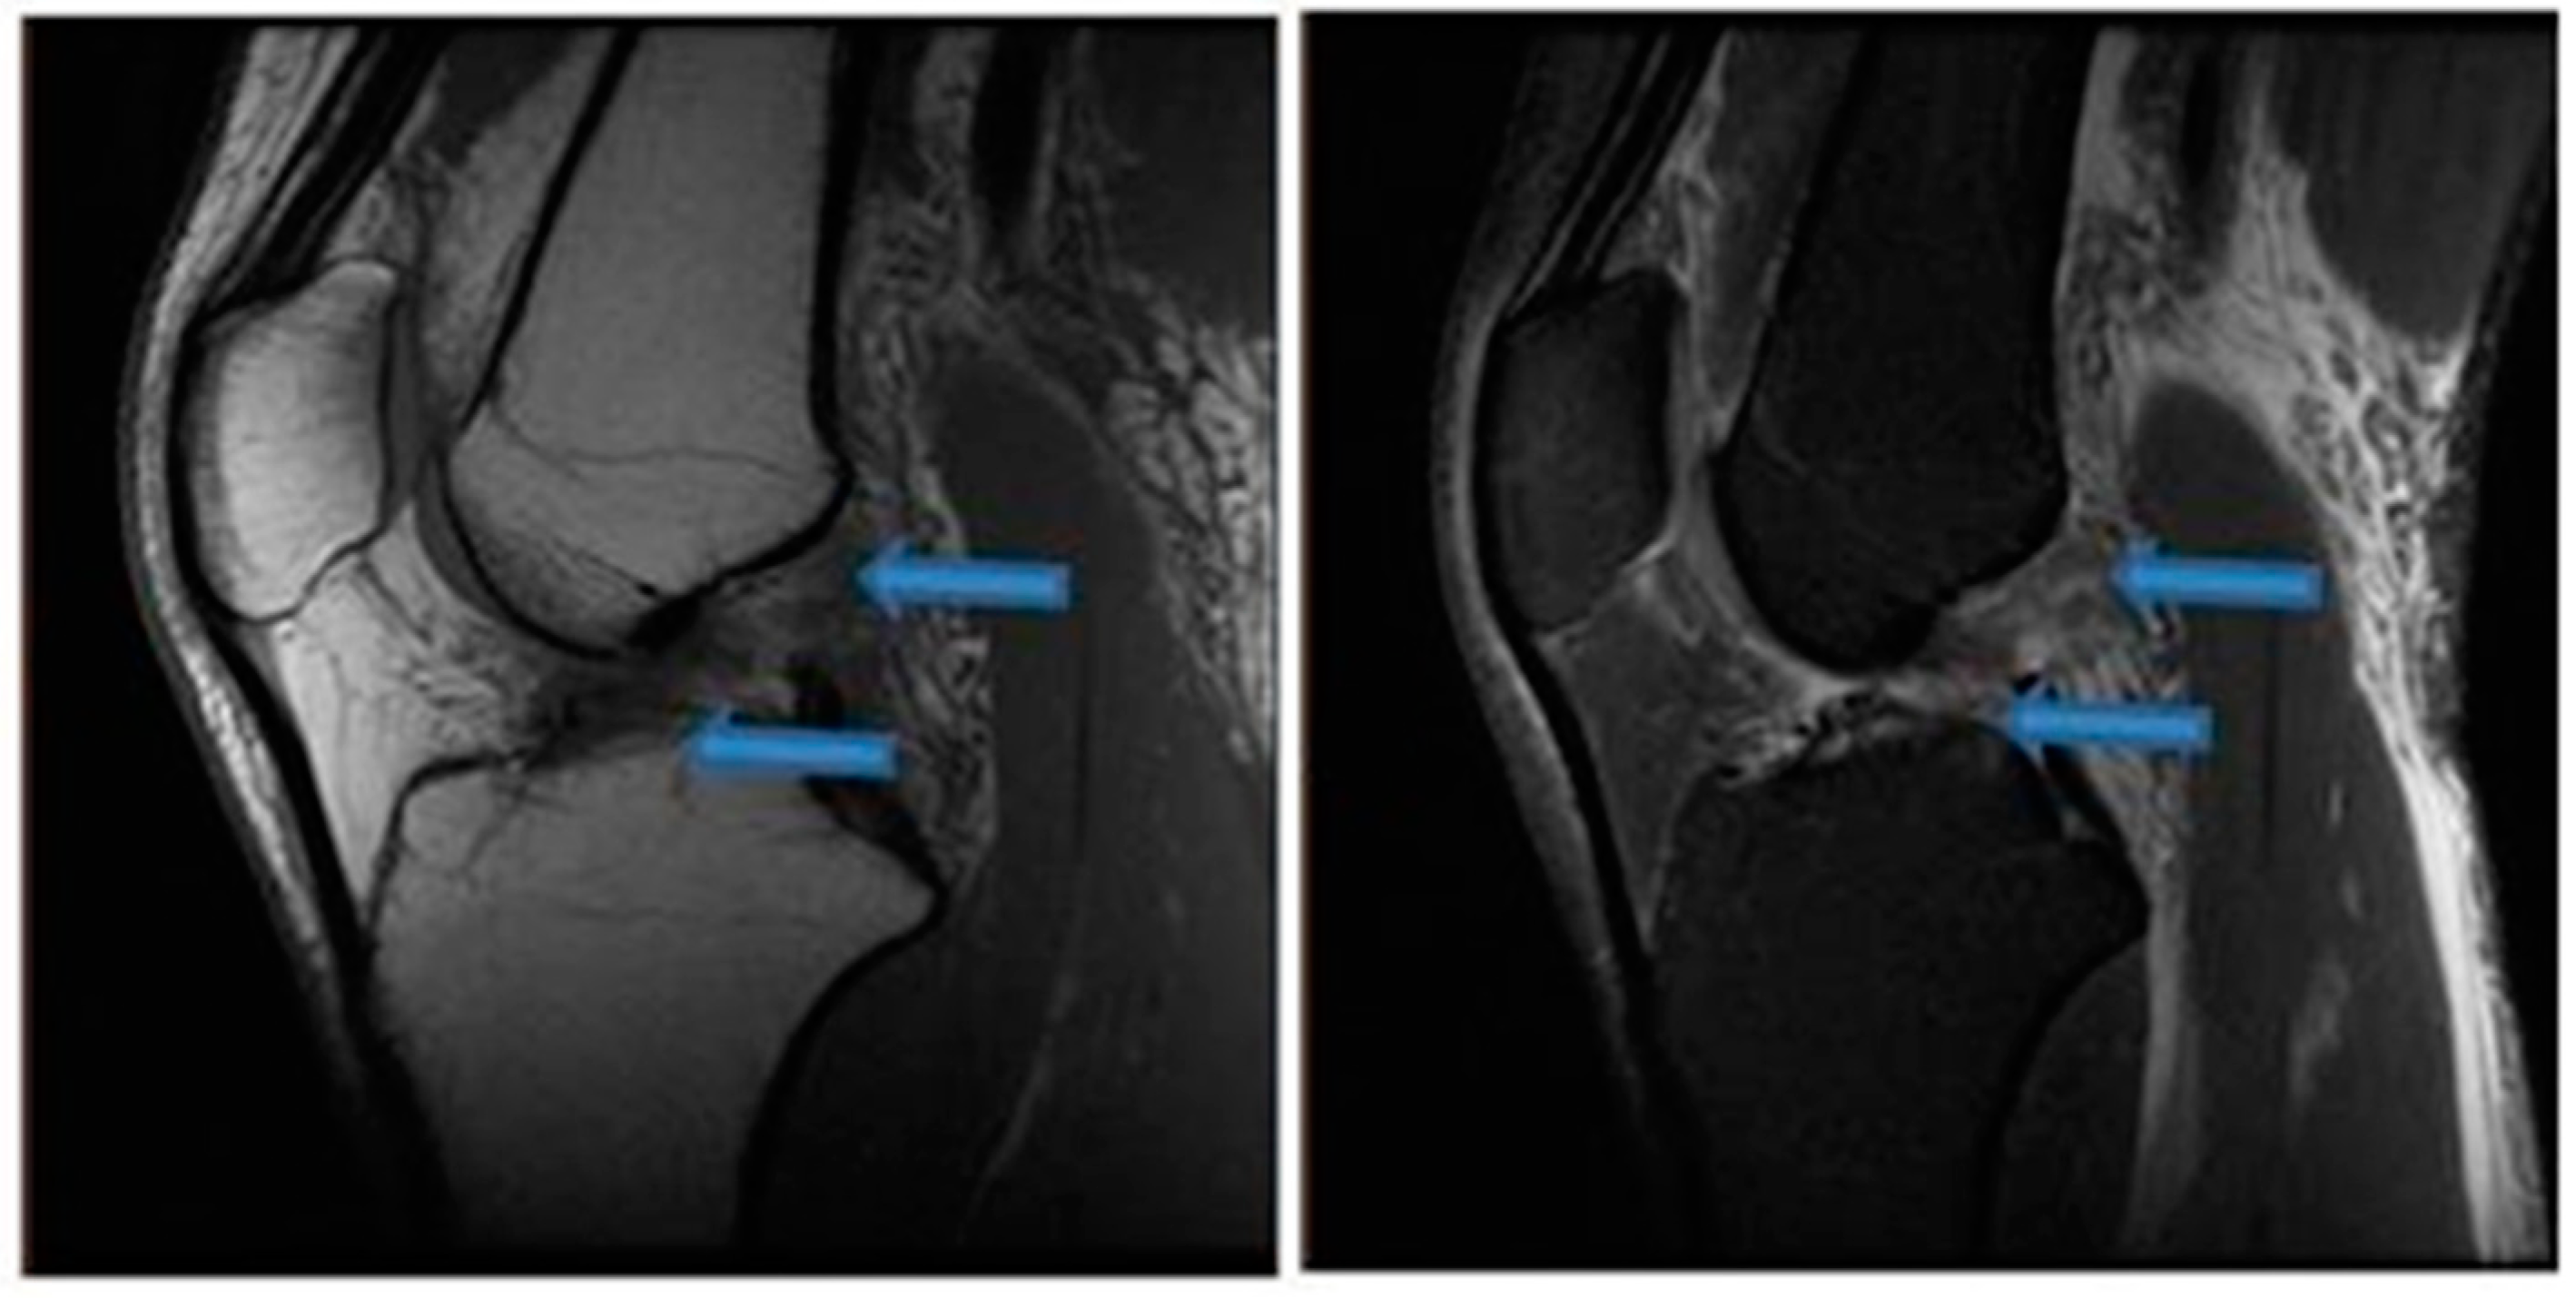

| 9 November 2020 | MRI scans demonstrating signs of partial ACL healing |

| 14 August 2021 | MRI scans demonstrating signs of complete ACL healing |

| 24 December 2021 | MRI scans confirming signs of complete ACL, MCL and medial meniscus healing |